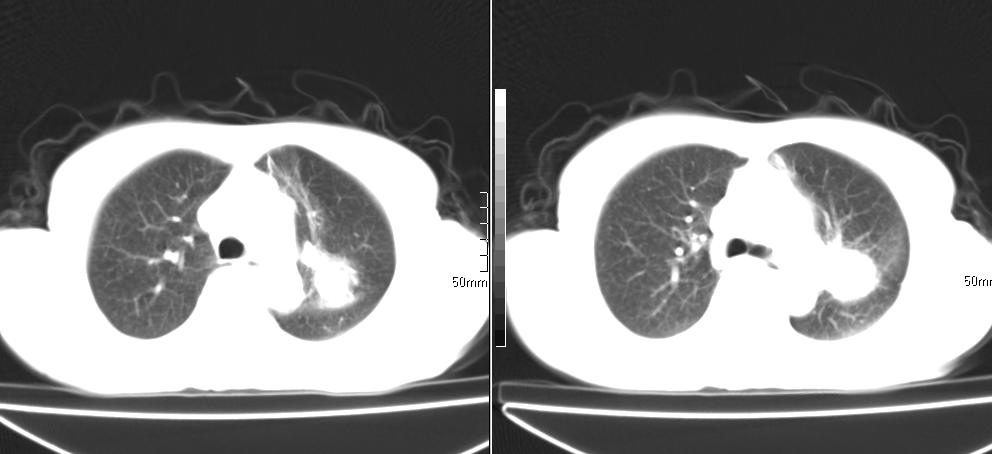

标题: CT26857:女,60岁,胃部不适前来就诊,不咳嗽,乏力,胸椎 [打印本页]

标题: CT26857:女,60岁,胃部不适前来就诊,不咳嗽,乏力,胸椎

1、胸椎有骨质破坏伴周软组织,考虑胸椎转移。2、考虑左肺上叶尖后段支气管开口区周围型肺癌可能。

中央肺癌

1、胸椎有骨质破坏伴周软组织,考虑胸椎转移。2、考虑左肺中央型肺癌可能。

支持中央型肺癌,胸椎转移。

1)考虑左肺中央型肺癌。2)胸椎转移瘤不排除;建议行mri检查。